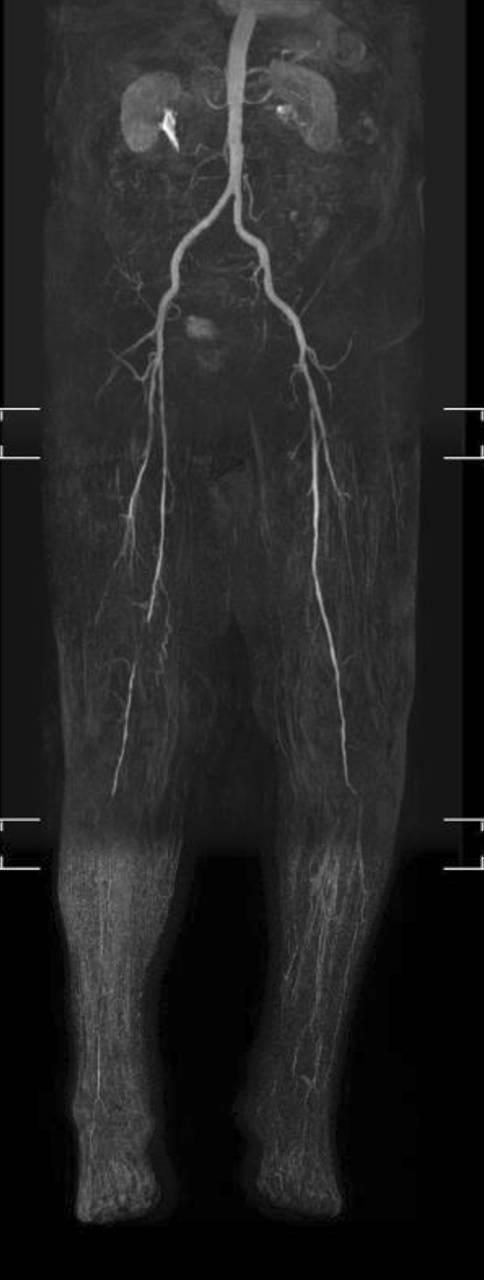

[糖尿病足综合征 - 第2部分:血运重建、治疗选择、护理结构、复发预防]

[Diabetic foot syndrome-Part 2 : Revascularization, treatment alternatives, care structures, recurrency prophylaxis].

Diabetic foot syndrome (DFS) is the most frequent reason for major amputations in Germany. The majority of foot lesions are triggered by repetitive pressure in diabetic polyneuropathy. Peripheral arterial occlusive disease (PAOD) impairs wound healing and is the main risk factor for amputations. The treatment of wounds and infections as well as timely revascularization are decisive. The use of endovascular and vascular surgical methods depends on the distribution pattern and length of the occlusion processes. Both procedures are complementary. Bypass surgery is of great importance for neuroischemic DFS. Multidisciplinary centers that provide revascularization in DFS can achieve an improvement of arterial blood flow in 90% of the cases and reduce the amputation rate by up to 80%. Due to the high recurrence rate of diabetic foot lesions, measures for secondary prophylaxis are of exceptional importance (podological and orthopedic technical care, foot surgery).

糖尿病足综合征(DFS)是德国进行大截肢手术最常见的原因。大多数足部病变是由糖尿病多发性神经病变中的反复压力引发的。外周动脉闭塞性疾病(PAOD)会损害伤口愈合,是截肢的主要危险因素。伤口和感染的治疗以及及时的血运重建是决定性的。血管内和血管外科方法的使用取决于闭塞过程的分布模式和长度。这两种手术方法相辅相成。旁路手术对神经缺血性DFS非常重要。在DFS中提供血运重建的多学科中心在90%的病例中可实现动脉血流改善,并将截肢率降低多达80%。由于糖尿病足病变的复发率很高,二级预防措施尤为重要(足部护理和矫形技术护理、足部手术)。